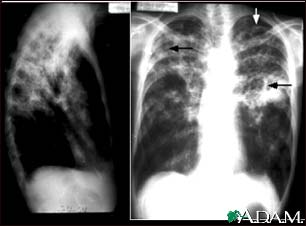

Tuberculosis, advanced - chest X-rays

Tuberculosis is an infectious disease that causes inflammation, the formation of tubercules and other growths within tissue, and can cause tissue death. These chest x-rays show advanced pulmonary tuberculosis. There are multiple light areas (opacities) of varying size that run together (coalesce). Arrows indicate the location of cavities within these light areas. The x-ray on the left clearly shows that the opacities are located in the upper area of the lungs toward the back. The appearance is typical for chronic pulmonary tuberculosis but may also occur with chronic pulmonary histiocytosis and chronic pulmonary coccidioidomycosis. Pulmonary tuberculosis is making a comeback with new resistant strains that are difficult to treat. Pulmonary tuberculosis is the most common form of the disease, but other organs can be infected.